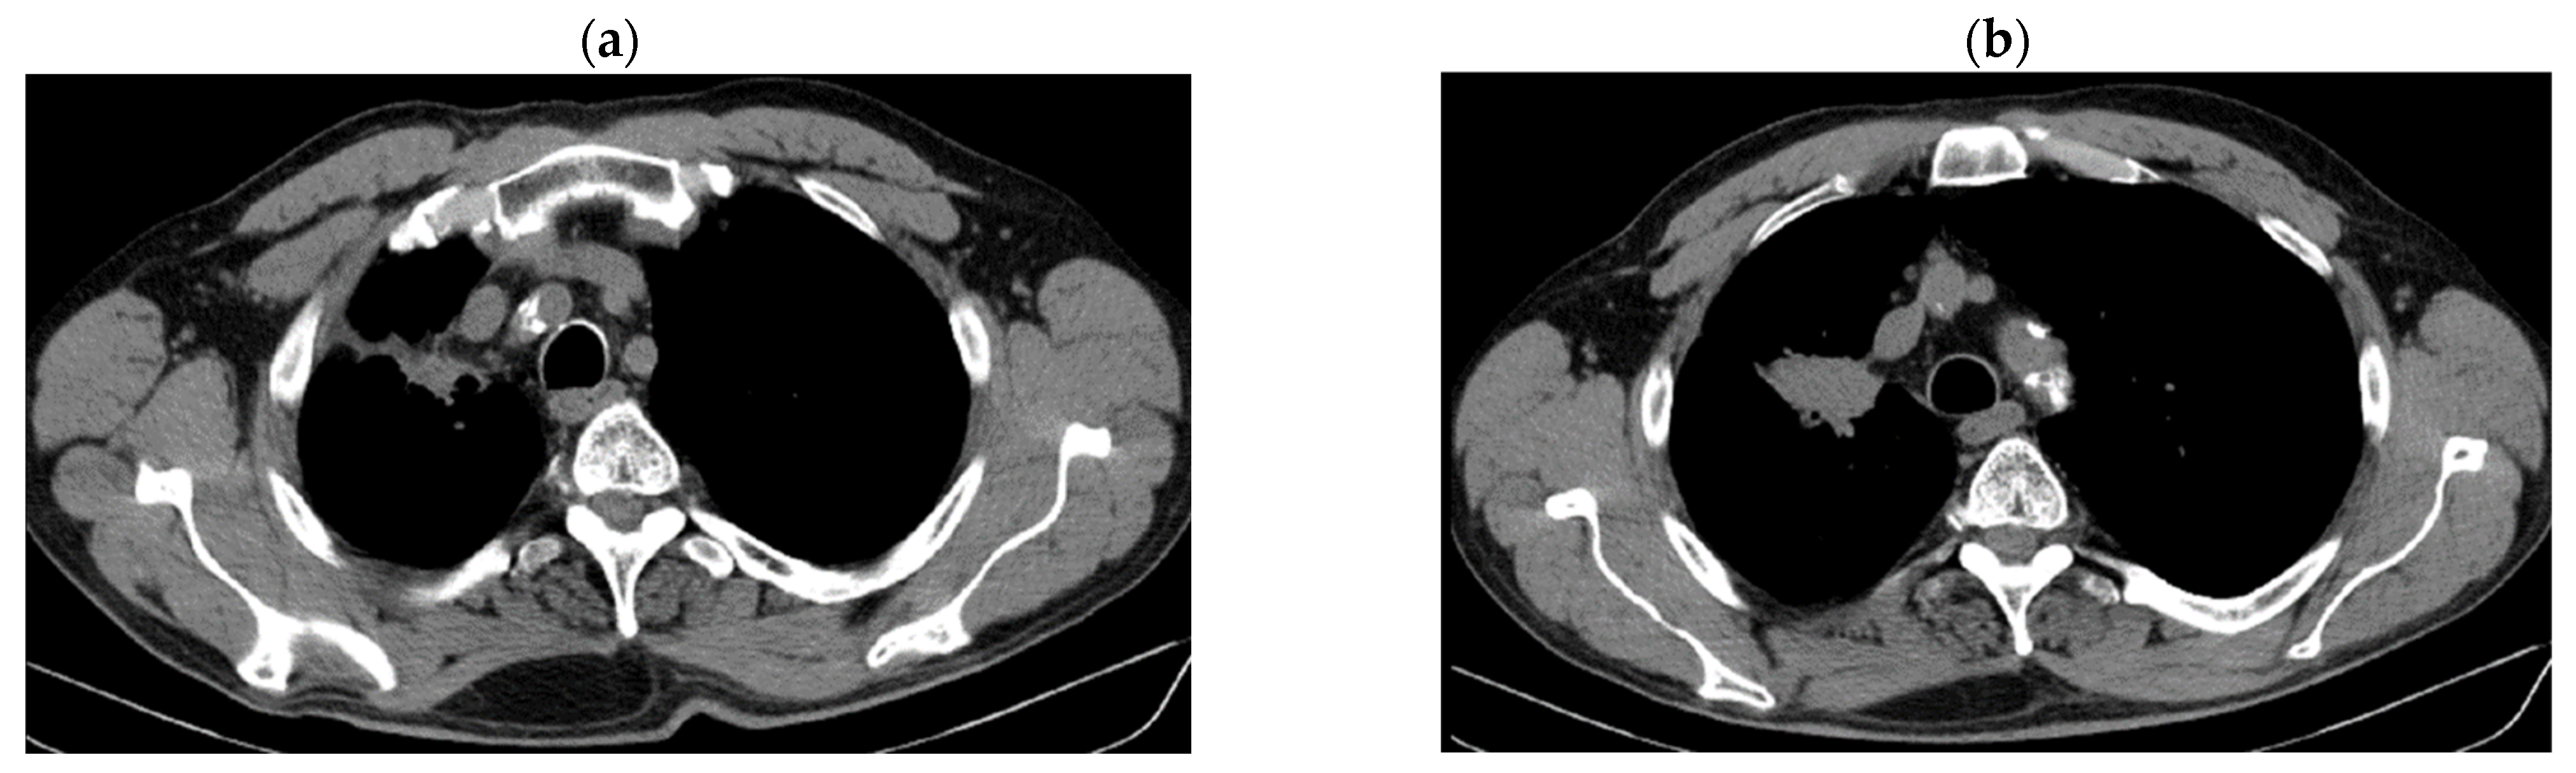

2. Case Presentation

2.1. Systemic Third-Line Therapy (4xDocetaxel) Was Initiated 04–07/2020

2.2. Monitoring 2022: Oncological Commission 1910/16.08.2022

2.3. Oncological Committee 07/25/2023 Recommended

- Consider rescue re-irradiation (SBRT), taking into account the current primary tumor dimensions of 24 × 34.2 mm on PET CT from 06/2023 and also the total dose previously administered (08–09/2020), the previously applied fractionation, the time between the two irradiations, the cellular repair time and the dose constraints for the organs at risk.